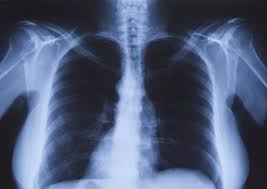

Oxipit Partners with CARPL to Increase Global Reach of AI Diagnostic Products

During the European Congress of Radiology, ECR2023, global medical imaging AI firm Oxipit announced that its diagnostic solutions will be available on the CARPL platform.